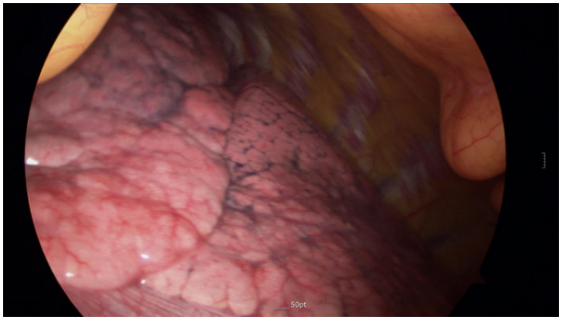

外科医生要求停止三次呼吸:一次是为了保护视野,另一次是为了楔形切除术。在潮气量为8mL/kg、呼吸次数为24-28次/min、空气/氧气比例为50:50的情况下,开始手动通气约1分钟,潮气末二氧化碳维持在25-28mmHg之间。当通气停止时,患者的肺保持静止并放气(图2)。在进行两次楔形切除术后,插入一根16Fr的胸导管。手术结束后,终止丙泊酚和瑞芬太尼的持续输注。

图2.使用视频辅助胸腔镜查看患者肺部图像。过度换气后,患者的肺保持静止和放气。